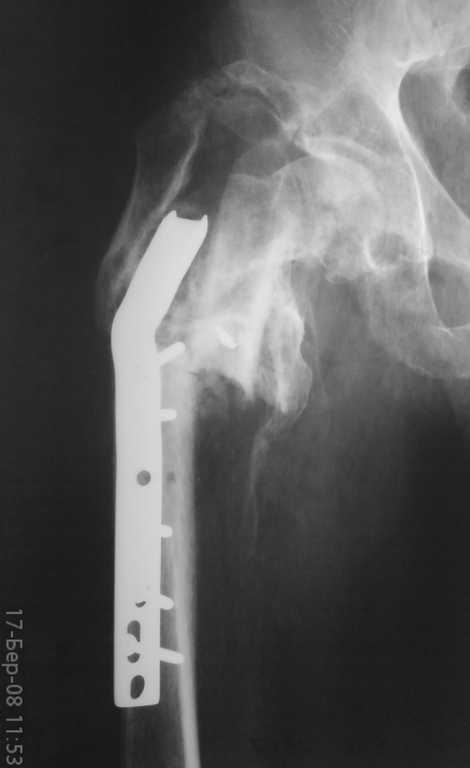

неправильно консолидированный перелом вертельной области

Ув.коллегиПоступил больной год назад прооперированный-МОС вертельной области.

Жалобы на невозможность ходьбы и сильное(15-18 см)укорочение ноги. Что делать? Заранее благодарен.Тарас Рокита ,Киевская ГБ 7

судя по снимкам укорочение должно быть около 7-8 см. Целесообразно выполнить читаемые снимки.

варианты лечения, на мой взгляд:

1 удаление пластины

2. остеотомия

3. низведение бедра в АВФ " таз- бедро"

4. первично ревизионое эндопротезирование.

К обсуждению 4 пункта будет целесообразно вернуться после выполнения первых трех.

Для начала определить величину и причину укорочения не по жалобам больного, а сделав соответствующие измерения и рентгеновские снимки,

КТ.

Проблема интересная, у нас в год проходят 3-5 в чем-то подобных ситуаций с проксимальнм отделом бедра.

Как общий подход - удаление несостоятельного фиксатора, восстановление длины и оси сегмента (не обязательно все это делать в области

несращения), окончательная фиксация.

В данном случае надо еще разбираться, что за "оссификаты" над большим вертелом, что за отломок на фоне шейки, что с суставом - можно

ли рассчитывать на движения после коррекции, или уже думать о протезе.

Можно ли организовать снимок таза и боковой снимок? Что за имплант, если Blade Plate тогда сколько градусный? Что намерены делать?